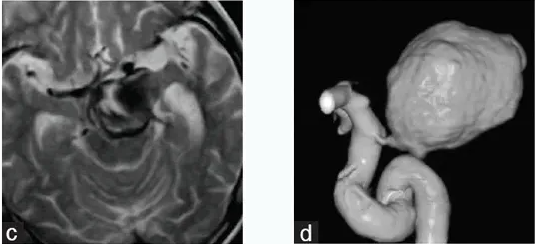

术前,川岛教授对王叔进行了全面体检,以评估整体健康状况。术中,川岛教授经左外侧裂入路的手术视野。动脉瘤切除术后,动脉瘤夹闭成功,血栓被清除。

术后CT显示,脑干解除占位效应,无缺血性病变